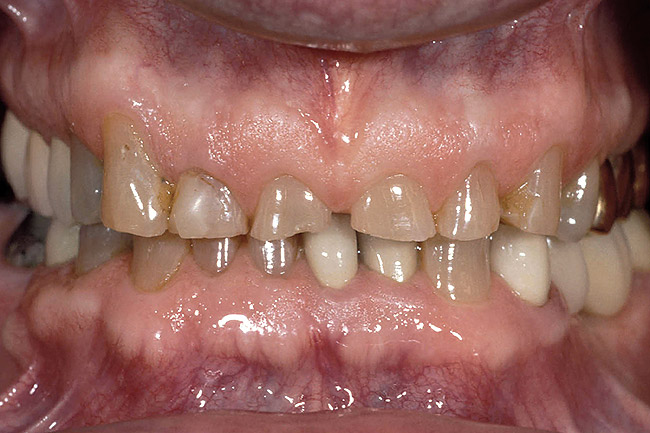

Figure 6  A patient presented with severe anterior wear and over-eruption. Esthetically, the maxillary centrals needed lengthening by 3 mm incisally.

Figure 6

Figure 8  Osseous crown lengthening was performed using the incisal edge position of the temporary to determine bone and gingival levels.

Figure 8

Figure 9  View at 10 weeks post-surgery showing the new gingival level. The preparation and temporary will now be extended to the gingival level.

Figure 9

Figure 10  The final restorations demonstrate the esthetic and functional changes from lengthening the incisal edges and raising the gingiva.

Figure 10